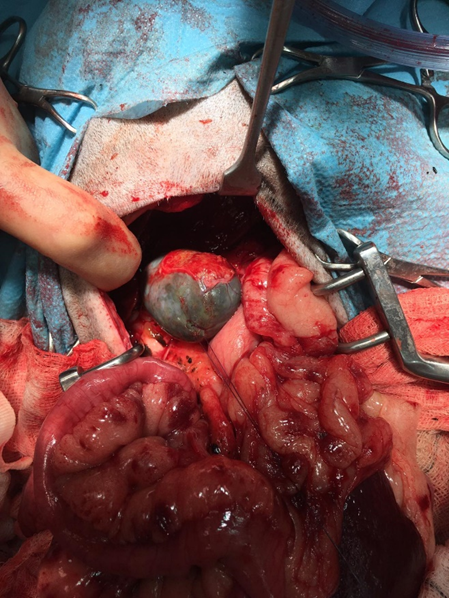

A diagnosis of biliary mucocoele was made. Coagulation parameters were normal and emergency surgery was recommended. At surgery the gall bladder was found to be ruptured and the diagnosis was confirmed grossly. Cholecystectomy was performed. The dog recovered well from surgery and made an excellent post operative recovery.

Normal bile is formed from mucous, cholesterol and bile salts. With biliary mucocoele the normally liquid mucus molecules are altered to produce cross-linking gelatinous bile that ultimately progresses to the point of a solid structure, often likened in appearance and consistency to a kiwi fruit. This can exist asymptomatically until it grows to a critical point where it obstructs outflow and/or causes pressure necrosis of the gall bladder wall when a crisis ensues.